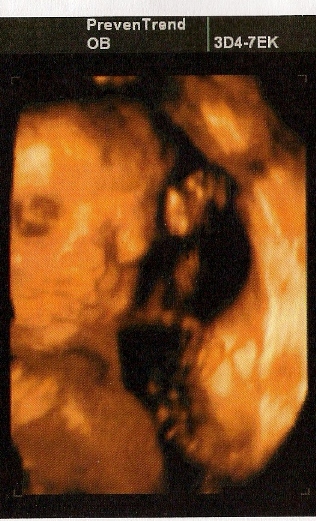

zapáné! szupiii képek..!ismerős!